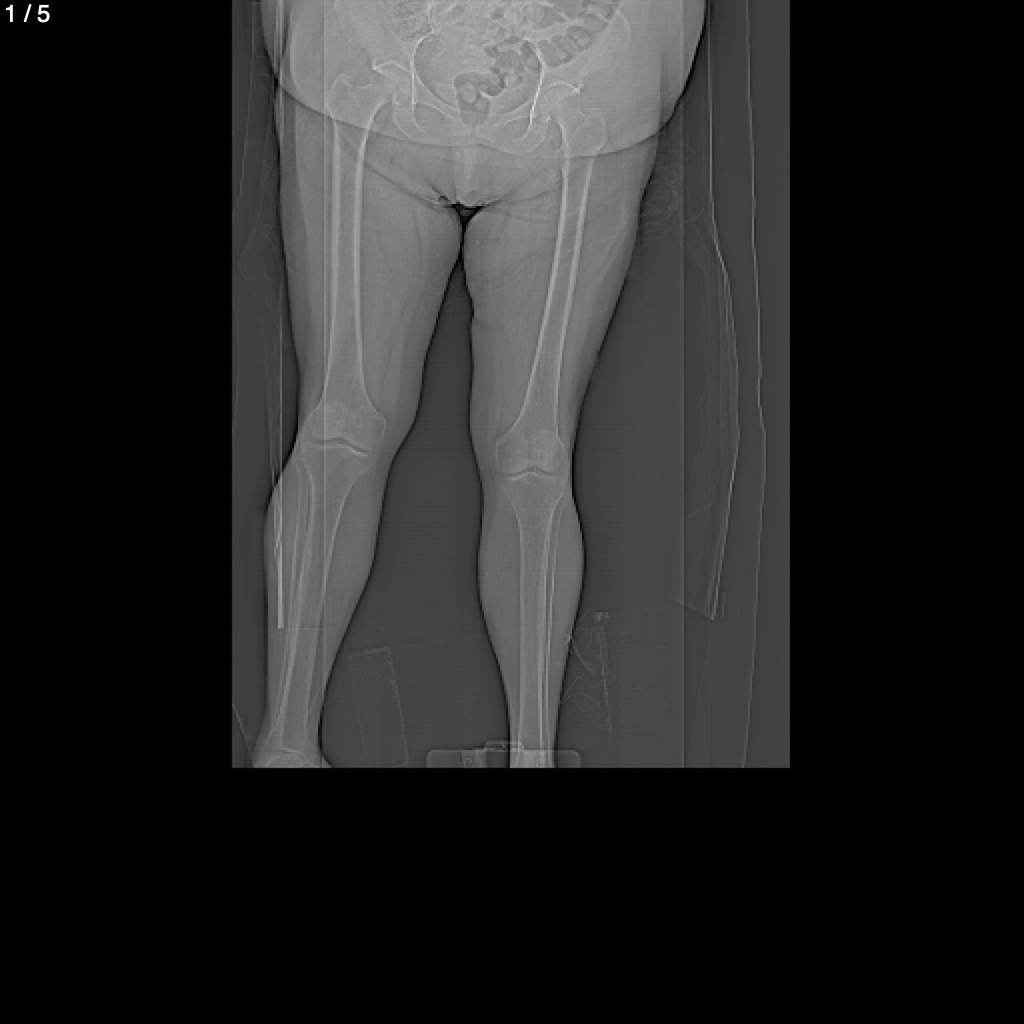

Blanca Estela Romero Rojas - Extremidades Inferiores Miembropelsimple (Adulto)